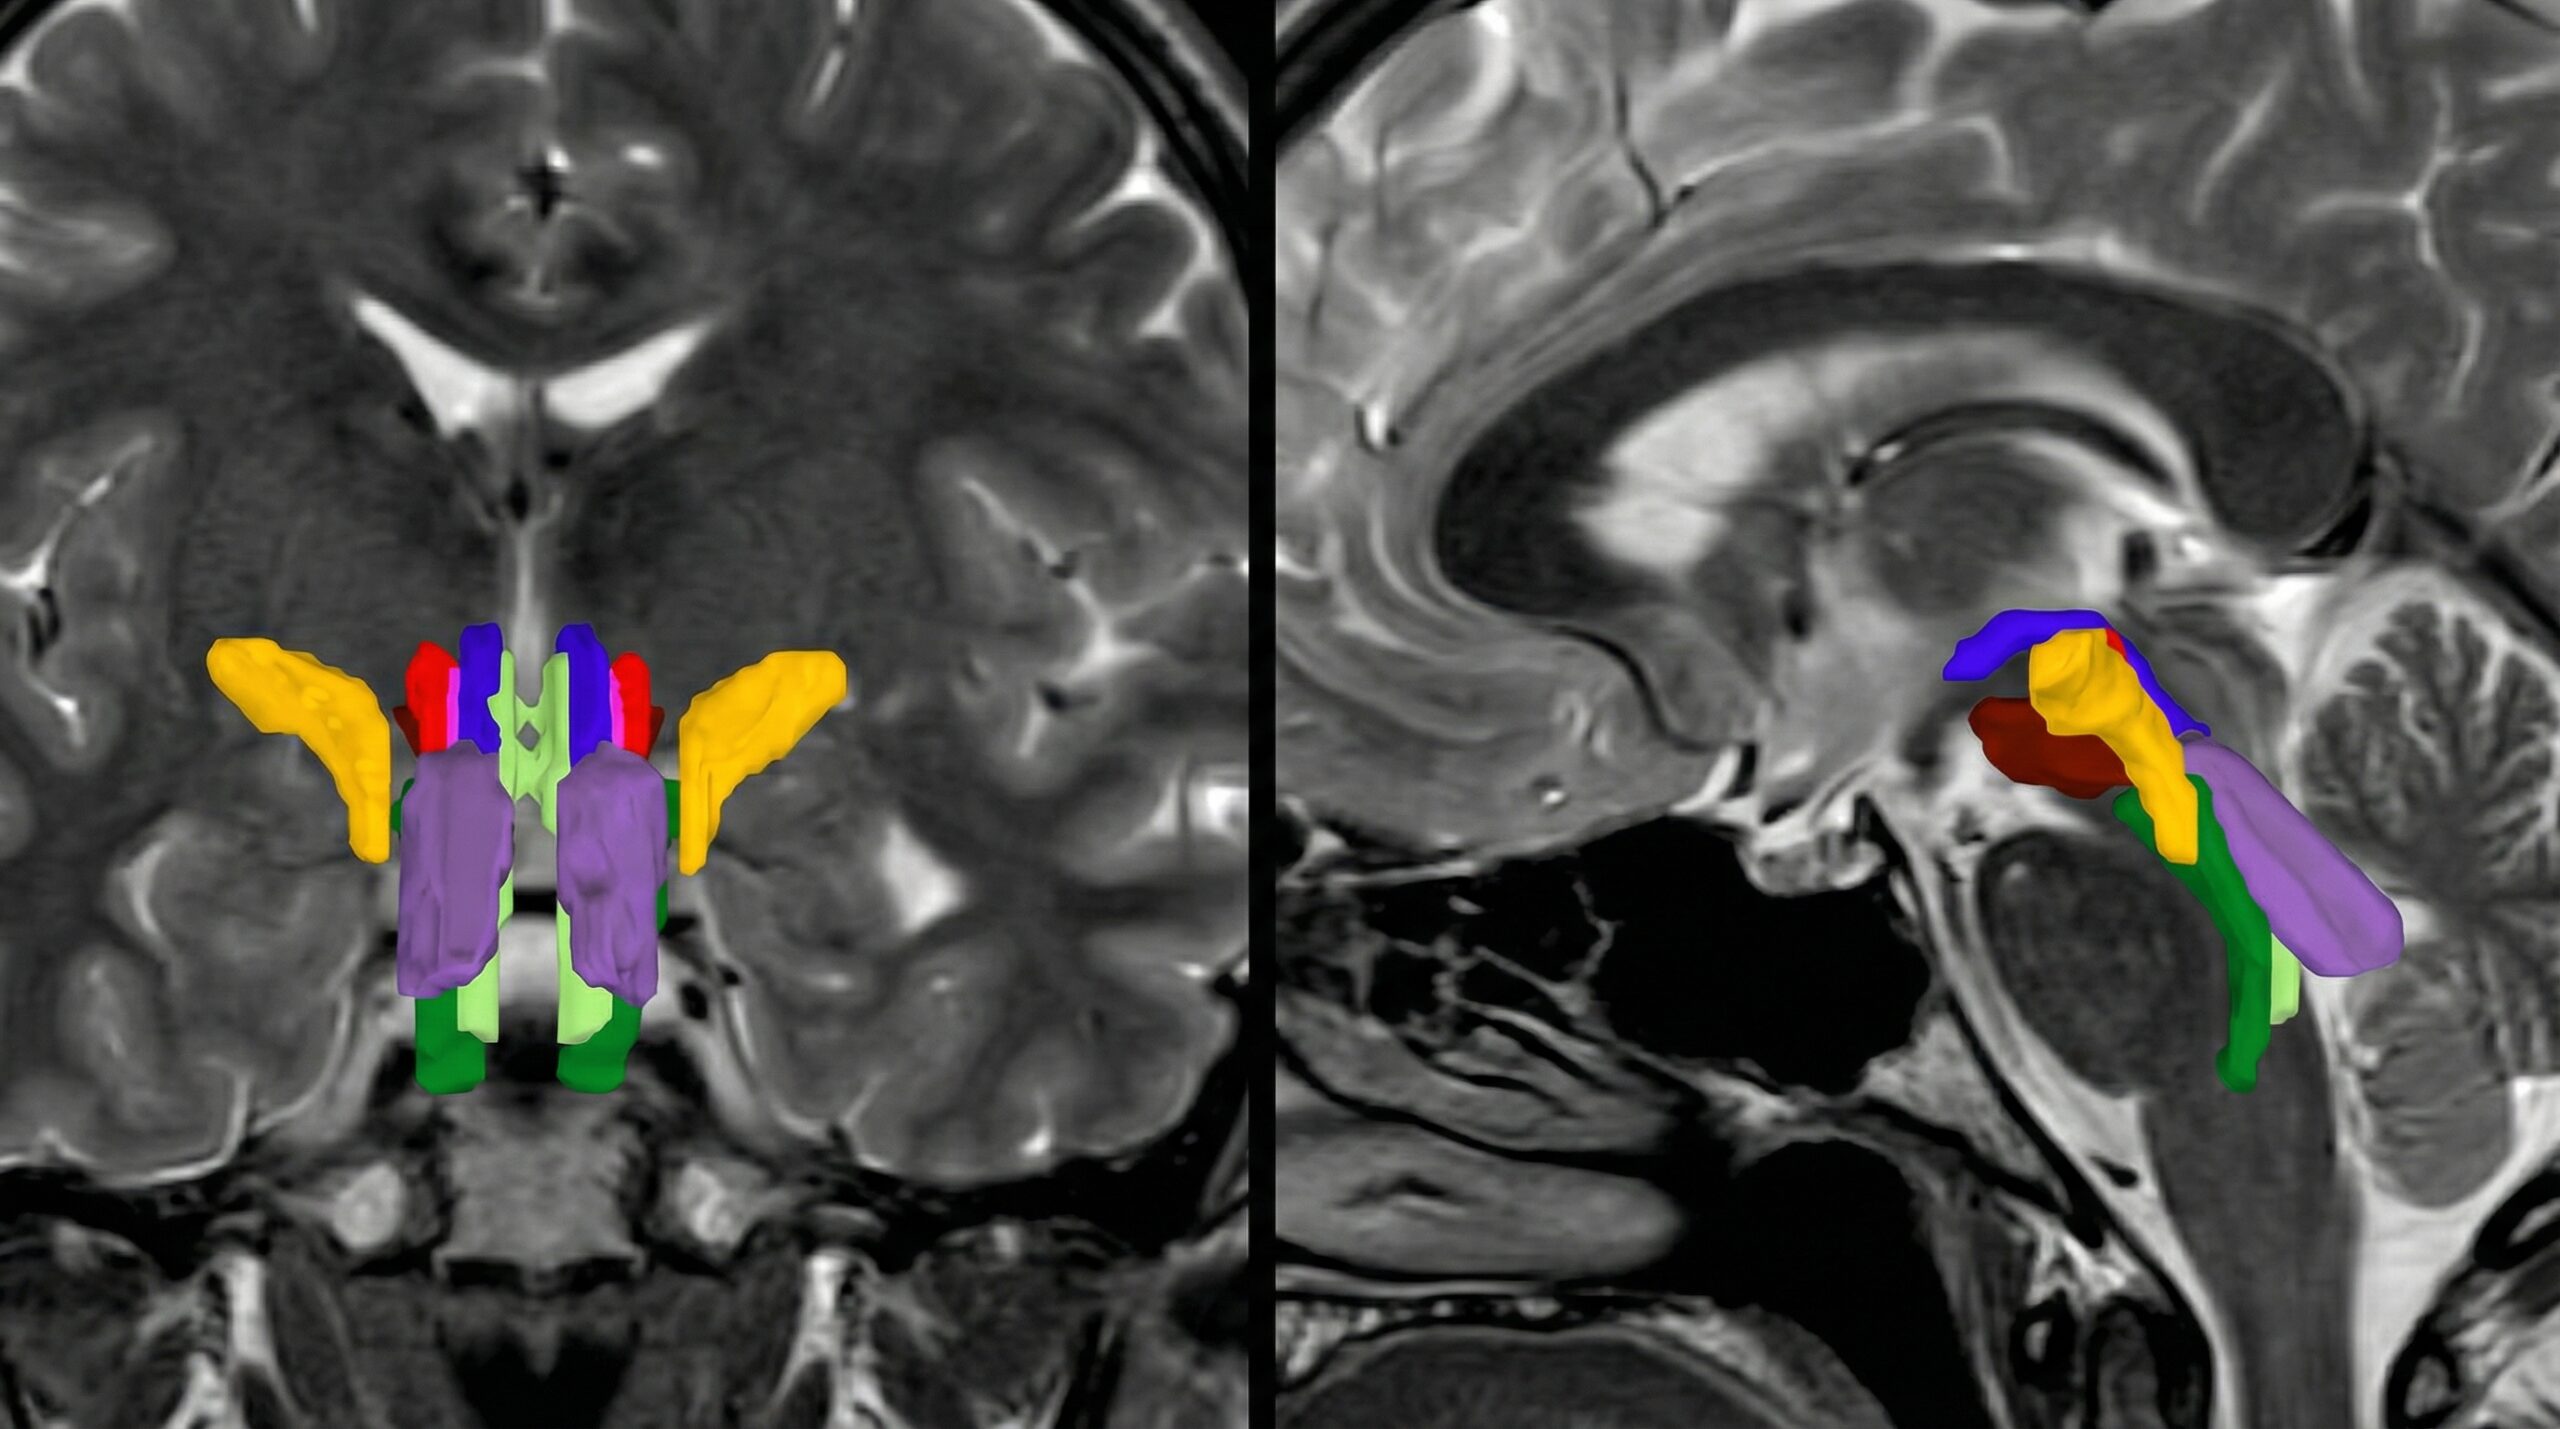

El tronco encefálico, una estructura diminuta pero vital, controla funciones básicas como la conciencia, la respiración y el ritmo cardíaco. Su estudio ha sido históricamente un reto debido a las limitaciones de las técnicas de imagen. Sin embargo, la BSBT, impulsada por IA, supera estas barreras. Analiza secuencias de resonancia magnética por difusión (dMRI) y, mediante una red neuronal convolucional (CNN), distingue estos haces cruciales, como el lemnisco medial o el tracto espinotalámico anterior.

Esta tecnología, más allá de la mera segmentación, genera un ‘mapa probabilístico de fibras’, rastreando axones desde regiones superiores del cerebro hasta el tronco encefálico. ¿Qué significa esto para tu negocio? Mayor precisión en la identificación de anomalías y una comprensión más profunda de enfermedades neurológicas. Si tu empresa desarrolla software de análisis de imagen médica o trabaja en el desarrollo de dispositivos de diagnóstico, este avance del MIT te interesa directamente.